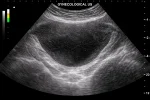

Современное комплексное УЗИ полового члена включает несколько режимов: B-режим для визуализации структур, допплеровские методы для оценки кровотока, а также метод B-потока для детального анализа динамики кровенаполнения тканей.

УЗИ полового члена является важным диагностическим методом, который позволяет оценить состояние тканей, сосудов и структур полового члена, выявить различные патологии и мониторить состояние пациента после лечения или операций.